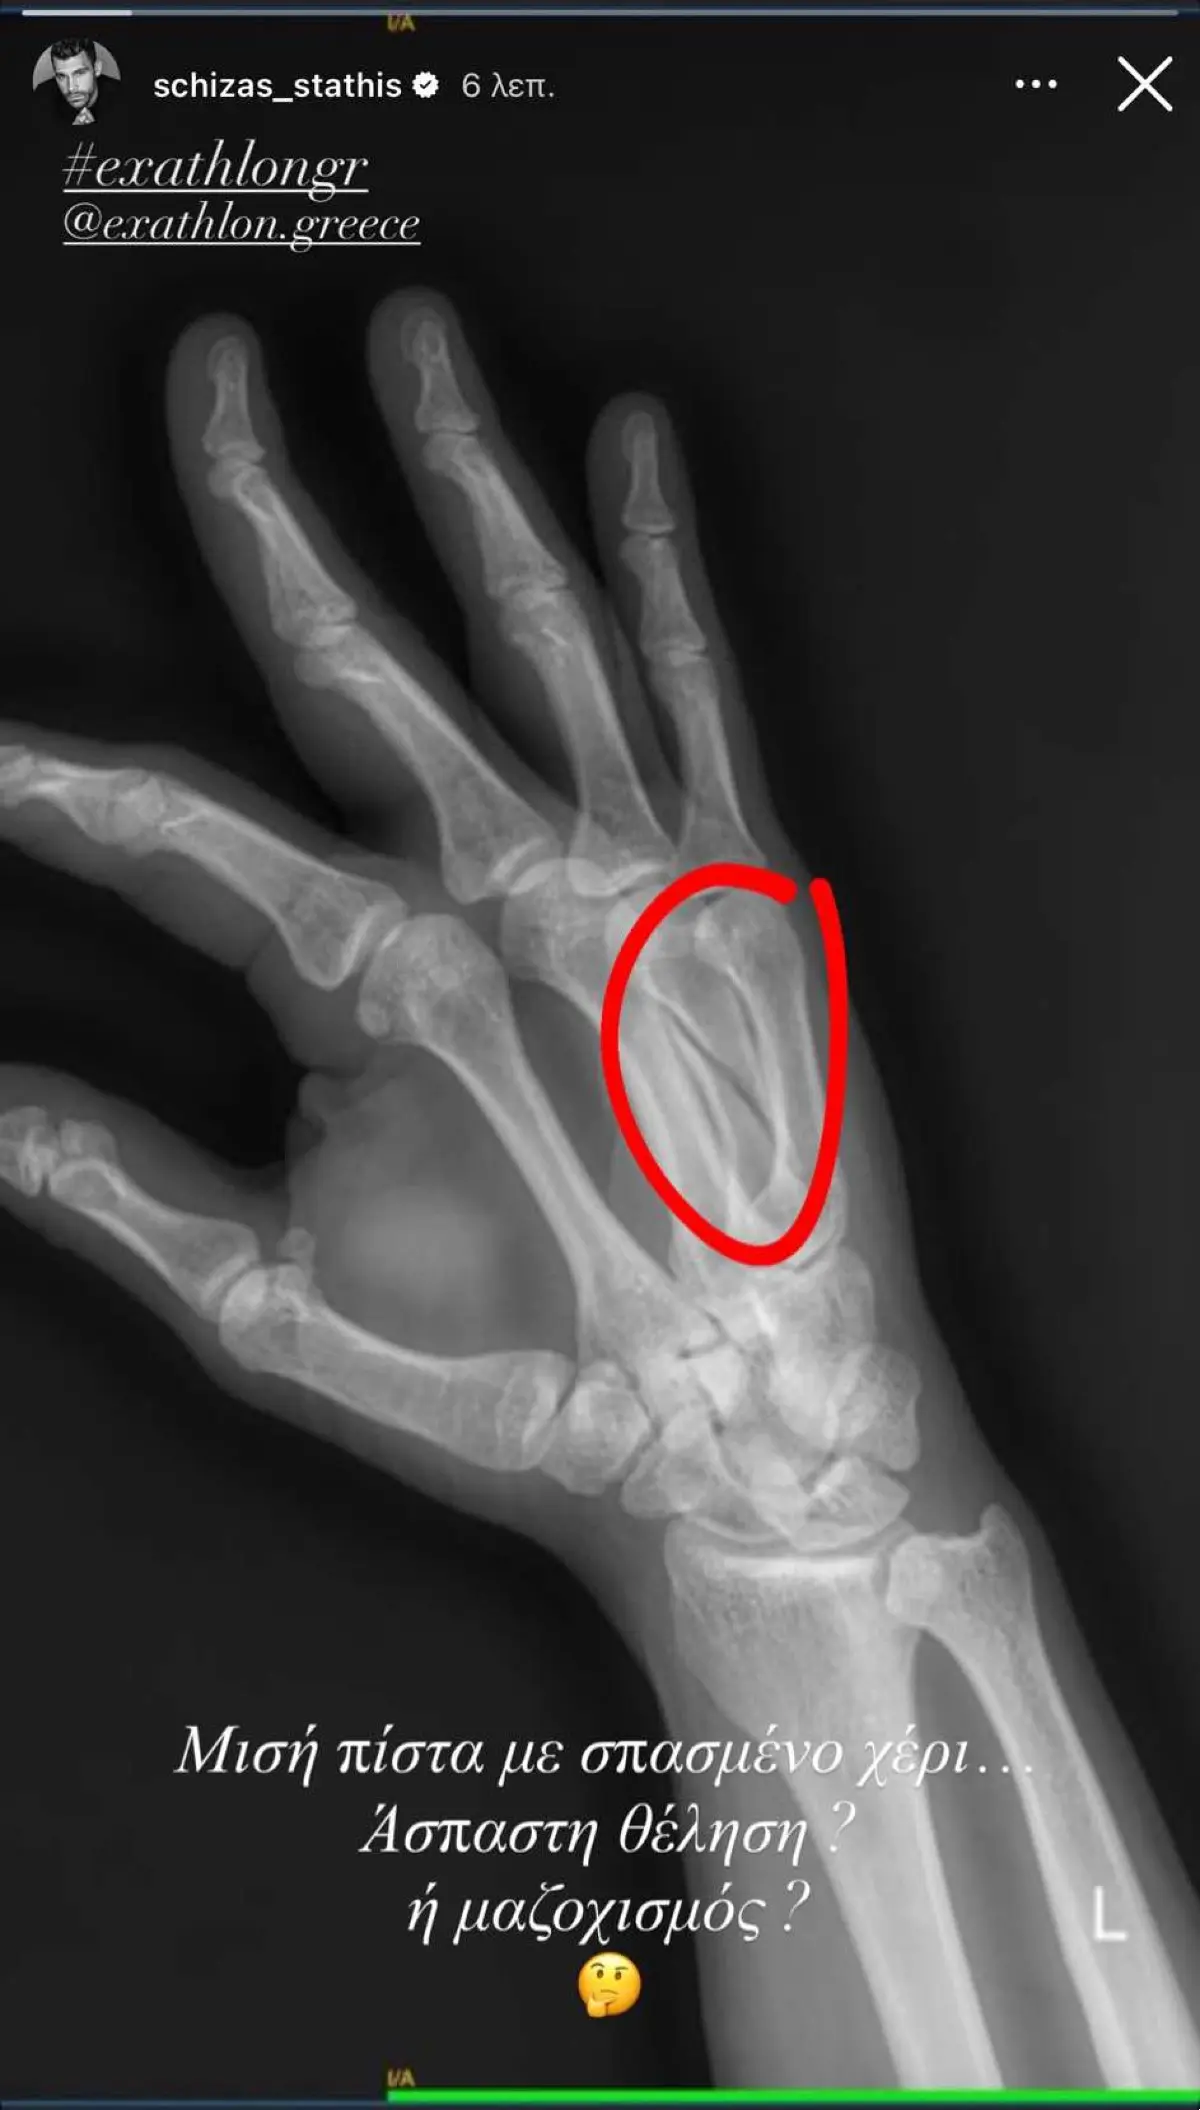

Η ακτινογραφία του Στάθη Σχίζα με τον σπασμένο του χέρι

Μετά την προβολή του επεισοδίου, ο Στάθης Σχίζας έκανε μία ανάρτηση στον προσωπικό του λογαριασμό στο Instagram, δημοσιεύοντας μία φωτογραφία από την ακτινογραφία του, όπου φαίνεται ξεκάθαρα το κάταγμα και έγραψε: «Μισή πίστα με σπασμένο χέρι… Άσπαστη θέληση ή μαζοχισμός;».